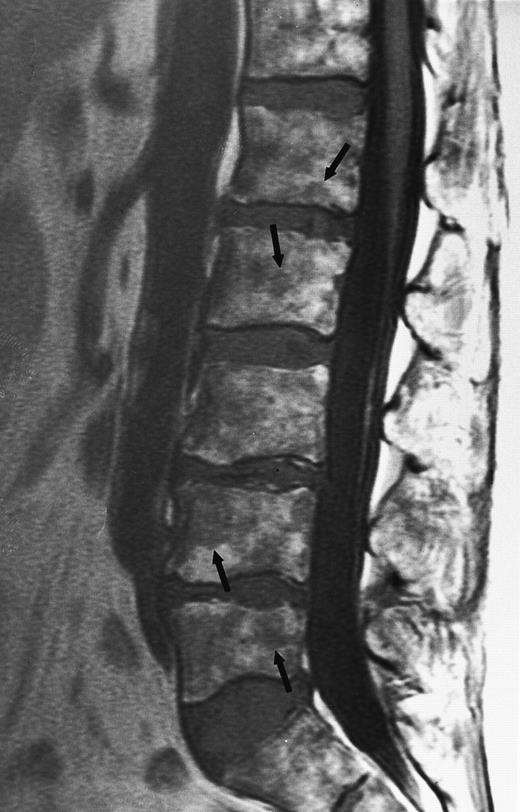

An 8-year-old boy with Burkitt's lymphoma and diffuse marrow involvement. Fat-suppressed, T2-weighted fast spin echo (3000/96, TR/TE) sagittal MR image of the lumbar spine shows heterogeneous signal intensity of the bone marrow and epidural extension of tumor (arrowheads) at the level of L5 and L2, with apparent preservation of the vertebral cortex.